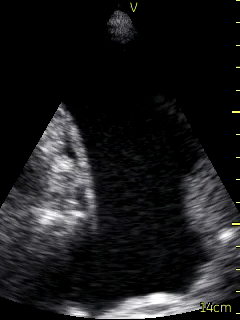

Ultrasound of the lung conducted by the Respirologist using a VScan device revealed a small amount of right pleural effusion and a moderate sized left pleural effusion. The ultrasound was used to landmark the site of needle insertion for thoracentesis (Figure 2, Video 2), at the 8th intercostal space, roughly 10 cm from the spine. Following anesthesia with lidocaine, the thoracentesis catheter was inserted along the same angle. A total of 500 ml was drained from the pleural space. The procedure was terminated as the patient began to experience some chest discomfort.  Following thoracentesis, ultrasound was repeated and there was no significant remaining fluid.  Sliding lung/pleura was visualized. The procedure was otherwise well tolerated. Fluid was sent for routine analysis, as well as cytology, flow cytometry, and cultures.